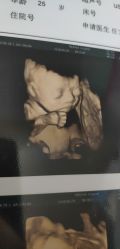

• -杭州贝瑞斯美华妇儿医院·早孕·产检·儿科

amanda1f1 上传于 19-11-01 | 报错